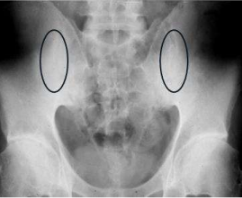

此症狀最常於僵直性脊椎炎病人,或跌坐造成兩側薦髂關節頃斜受力不均,而造成兩側薦髂關節不等高甚至骨盤不對稱現象,在長時間步行後更容易引發其不對稱之薦髂關節疼痛現象,但不致於引起坐骨神經痛的症狀。(參見圖 4)

圖 4 雙側之薦髂關節炎(如圖圈所示)

(五) 僵直性脊椎炎

僵直性脊椎炎為基因體質性之脊椎縱韌帶發炎鈣化性之脊椎變化。一般常為 20 歲左右發病,臨床上表現由薦髂關節開始有疼痛現象,由 X光片上顯示薦髂關節之發炎性病變(參見圖 4),隨病理發展逐漸往腰椎、胸椎及頸椎漫延,因脊椎前縱韌帶之變化速度比後縱韌帶快,導致頸胸脊椎逐漸呈現前彎駝背現象。(參見圖 5)